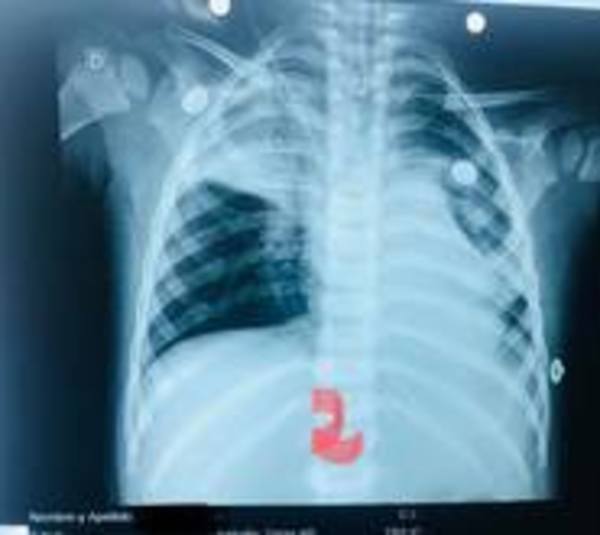

instituto nacional de enfermedades respiratorias